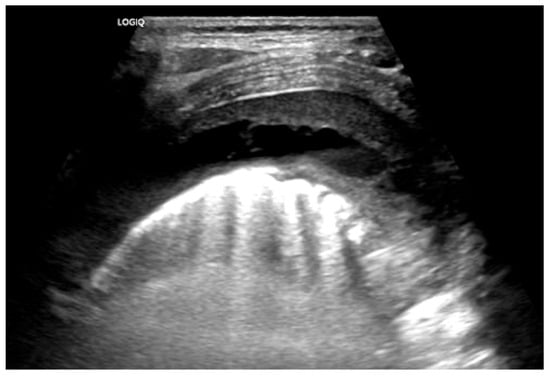

- Carrard, J.; Bacher, S.; Rochat-Guignard, I.; Knebel, J.-F.; Alamo, L.; Meuwly, J.-Y.; Tenisch, E. Necrotizing pneumonia in children: Chest computed tomography vs. lung ultrasound. Front. Pediatr. 2022, 10, 898402. [Google Scholar] [CrossRef]

- Kurian, J.; Levin, T.L.; Han, B.K.; Taragin, B.H.; Weinstein, S. Comparison of ultrasound and CT in the evaluation of pneumonia complicated by parapneumonic effusion in children. Am. J. Roentgenol. 2009, 193, 1648–1654. [Google Scholar] [CrossRef] [PubMed]

- Lai, S.-H.; Wong, K.-S.; Liao, S.-L. Value of lung ultrasonography in the diagnosis and outcome prediction of pediatric community-acquired pneumonia with necrotizing change. PLoS ONE 2015, 10, e0130082. [Google Scholar] [CrossRef]